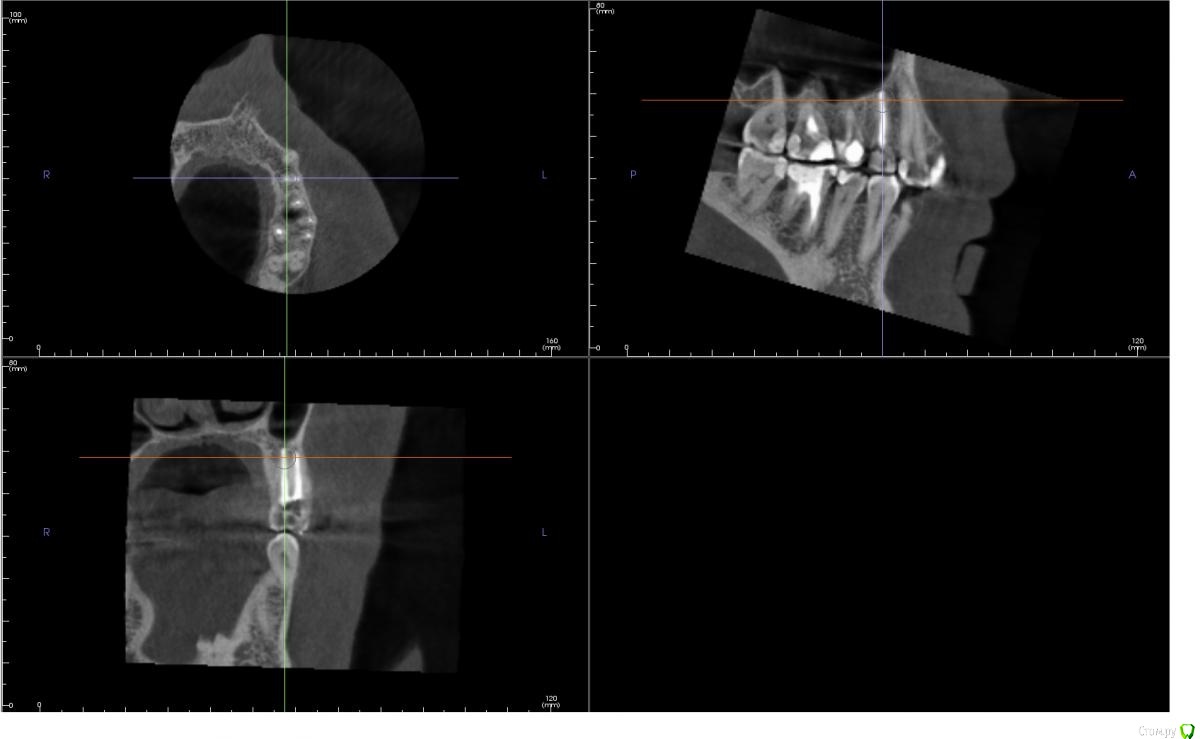

andreymir Опубликовано 7 марта, 2021 Поделиться Опубликовано 7 марта, 2021 Было проведено лечение каналов из-за кисты на 24 зубе. 2 канала, 2 корня. На КТ каналы запломбированы, но между каналами на всем протяжении каналов прослеживается затемнение. В описании, ранее сделанного КТ (в процессе лечения) рентгенологом указано, что корни срослись (каналы?) на всем протяжении. Затемнение между каналами на всем протяжении зуба на ранее сделанном КТ, к которому было приложено данное описание, не прослеживается. Это затемнение обнаруживается только на КТ, выполненном сразу после лечения. Затемнение между каналами на последнем КТ выходит за границу зуба, за границу кости и сливается с синусом. Скрины с КТ прилагаю к данному сообщению.Вопросы:1. Что это за затемнение? Не мог же появится новый канал в процессе лечения? Или это не заполненная пломбировочным материалом часть канала? Или это полость, которая соединяет каналы на всем протяжении?2. Верно ли, что раз затемнение выходит за границу зуба, то это означает, что стоматолог "перестарался", проткнул кость и провалился в синус? И теперь через весь зуб проходит не заполненный пломбировочным материалом канал связанный с синусом?3. Что делать с таким зубом? Можно ли ставить коронку, его нужно перелечить или он безнадежен и его пора менять на имплант?Спасибо!КТ ниже выполнено сразу после ЗАВЕРШЕНИЯ леченияКТ ниже выполнено в ПРОЦЕССЕ леченияЕсть КТ до начала лечения, если необходимо могу приложить в следующем сообщенииХорошего дня! Ссылка на комментарий

andreymir Опубликовано 7 марта, 2021 Автор Поделиться Опубликовано 7 марта, 2021 (изменено) у вас все нормально, не ищите проблем там где их нет. Зуб восстанавливайте искусственной коронкойБольшое спасибо вам за ответ, но я был бы вдвойне признателен за более обстоятельный ответ. Меня слегка тревожит первое изображение. Можете уточнить, что за затемнение проходит через весь зуб между двумя каналами на первом изображении и выходит в синус? Спасибо! Изменено 7 марта, 2021 пользователем andreymir Ссылка на комментарий